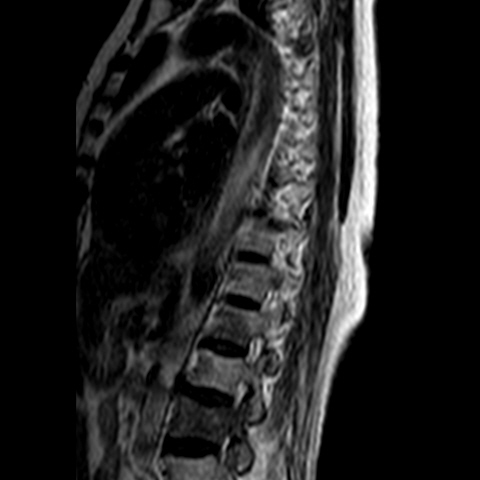

Needed help for this currently admitted 60 years old woman with gradual paralysis and severe back pain for the last few weeks. On examination there was slight gibbus and absent lower limb reflexes and MRI shows a lesion at L3 as well as T3.

Radiological images: